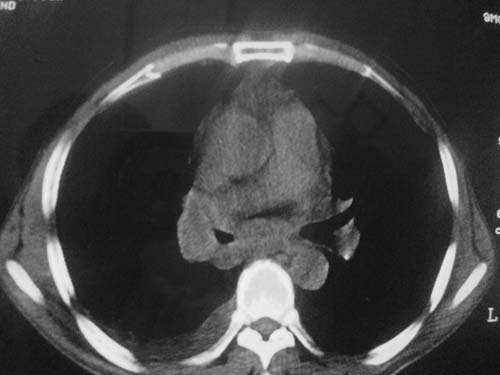

以下是引用科室第一人在2010-3-25 20:30:00的发言:[br]1:纵膈肿瘤性病变,恶性胸腺瘤可能性大伴纵膈右肺门淋巴结转移,右侧胸腔积液。[br]2:右侧肺门肿瘤性病变,纵膈淋巴结转移,右侧胸腔积液。右下叶转移。

以下是引用子期在2010-3-25 21:00:00的发言:[br]先考虑右中央型肺癌伴转移。

以下是引用江广1996在2010-3-25 22:49:00的发言:[br]通常肺癌向纵隔转移多见,纵隔肿瘤向肺内转移少见(有的表现为向肺内侵润)。本例以一元论考虑:右中心型肺癌并纵隔淋巴等多处转移。[br][br][本贴已被 江广1996 于 2010-3-25 22:50:07 修改过]

以下是引用yangyudong333在2010-3-26 6:43:00的发言:[br]“冰冻纵膈”,考虑纵膈淋巴瘤伴肺内及胸膜侵润。